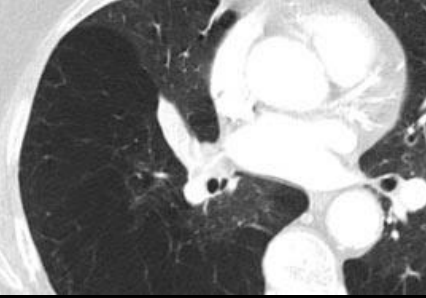

Panlobulillar